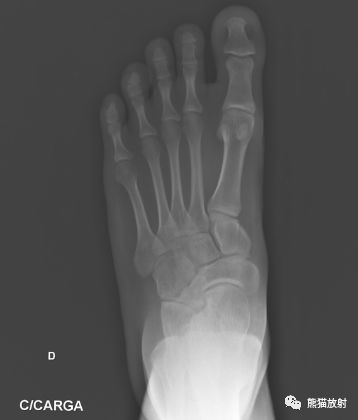

足正侧位平片

拍摄足负重正侧位,45°内斜位,跟骨轴位X线片。

跟距联合在侧位X线片上呈现C征,跟骨轴位观察跟距联合。